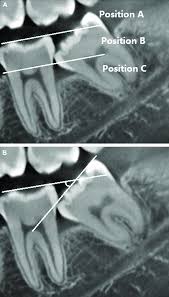

Türk Diş Hekimleri Birliğinin önerdiği fiyat tarifesine göre gömülü diş çekim ücretleri iki kategoride değerlendirilmektedir. Gömülü diş çekim operasyonu ve kemik retansiyonlu gömülü diş çekim operasyonu olarak sıralanır. Mukoza retansiyonu olarak değerlendirilen ilk grupta genellikle daha kısa sürede bitecek ve risk oranı düşük vakalar belirtilmektedir. Kemik retansiyonunun bulunması ise vakanın daha zor ve riskli olduğunu gösterir. Akademik sınıflandırmada ise kemik retansiyonları çok daha alt kategorilerde değerlendirilmektedir. Kısmen kemik içinde bulunan gömülü dişin çevre dokular ve yan diş ile ilişkisine göre çeşitli risk seviyeleri bulunmaktadır. Bazı operasyonlar için 5 dk yeterli olmakla birlikte bazı durumlarda çevre dokulara zarar vermemek adına 30 dk ila 45 dk arasında süren bir işlem gerekmektedir.

Literatürde bu konuya çeşitli yaklaşımlar bulunmaktadır. Profilaktik gömülü diş operasyonu adı altında bütün 20 yaş dişlerinin çekilmesi gerektiğini savunan çalışmacılar bulunmaktadır. Ancak kar zarar dengesi açısından değerlendirildiğinde gömülü diş operasyonu sonrası bölgede daha fazla zarar ortaya çıkma ihtimali varsa, rutin kontrolleri sağlamak şartı ile takip edilmesi önerilmektedir. Ancak çeşitli sebeplerde derin çürükleri bulunan kanal tedavisinin mümkün olmadığı durumlarda ve ciddi diş eti iltihabına bağlı olarak ağrı ve rahatsızlık veren vakalarda her türlü risk alınarak çekim planlanır. Ortodontik tedavi öncesi tedaviyi planlayan hekim tedavi sonrası nüks riski görüyor ise gömülü dişlerin çekilmesini uygun görebilir. Özellikle alt 20 yaş dişleri horizontal olarak gömülü kaldığı durumda önündeki 7 numaralı ikinci büyük azı dişini çürütmeye başlar. Çürük başlangıcı farkedildiğinde çekim kararı verilmelidir ancak bazı durumlarda horizontal konumda olan gömülü diş ile 7 numara arasında mesafe gözlenirse takip kararı verilebilir.